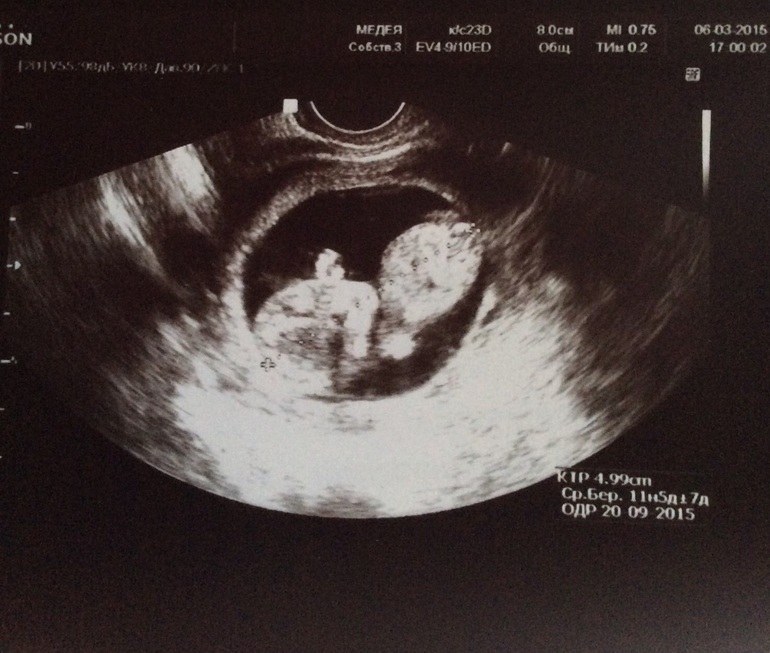

У нас ктр 54 мм в 12 нед. с копейками. Не вижу причин для паники, тем более какая-то девочка сказала)

Это не плодное яйцо, вы что?!!! размер пя определяют только до тех пор, пока не визуализируется эмбрион, а потом смотрят димамику роста малыша-ктр. Ему там тесно еще долго не будет))

Гаечка

Знакомтесь, это матка с плацентой) там и живет Ваш ребенок. Они будут расти вместе с малышом)) причем оболочка мягкая и он будет упираться конечностями, потягиваться например) конечно под конец малышу станет тесно, но там уже и роды на носу) слушайте девочек поменьше, озадачили нас всех)))

Вот, фото не очень конечно, как- то вкривь, но все четко обтекает хомячка))

А вот со спины)